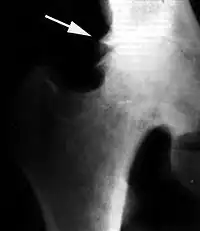

Краевые разрастания (остеофиты) при коксартрозе

Ранним рентгенологическим симптомом являются краевые костные разрастания — остеофиты — следствие активной пролиферации периферических отделов суставного хряща. Они проявляются вначале заострением краёв суставных поверхностей, а затем, нарастая, образуют массивные костные шипы и губы. Краевые остеофиты, как правило, раньше обнаруживаются со стороны суставных впадин.